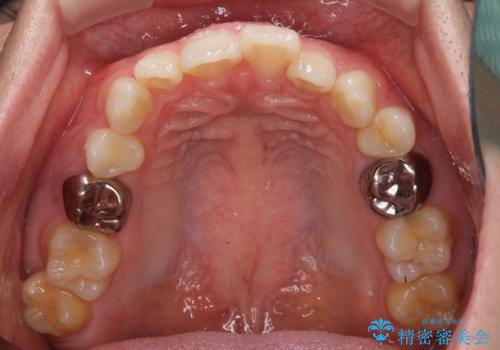

- 咬み合わせと前歯のデコボコを気にして来院された患者様です。

前から5番目の永久歯が3本欠損しており、乳歯が残存している状態でしたが、インビザラインでも十分に対応可能と判断し、インビザラインにて矯正治療を行うこととしました。

右下の残存している乳歯は萌出しきれておらず、全く咬み合っていない状態であり、インビザラインにて移動できない可能性があるため、ワイヤー矯正の併用も念頭に置いて治療を開始しました。